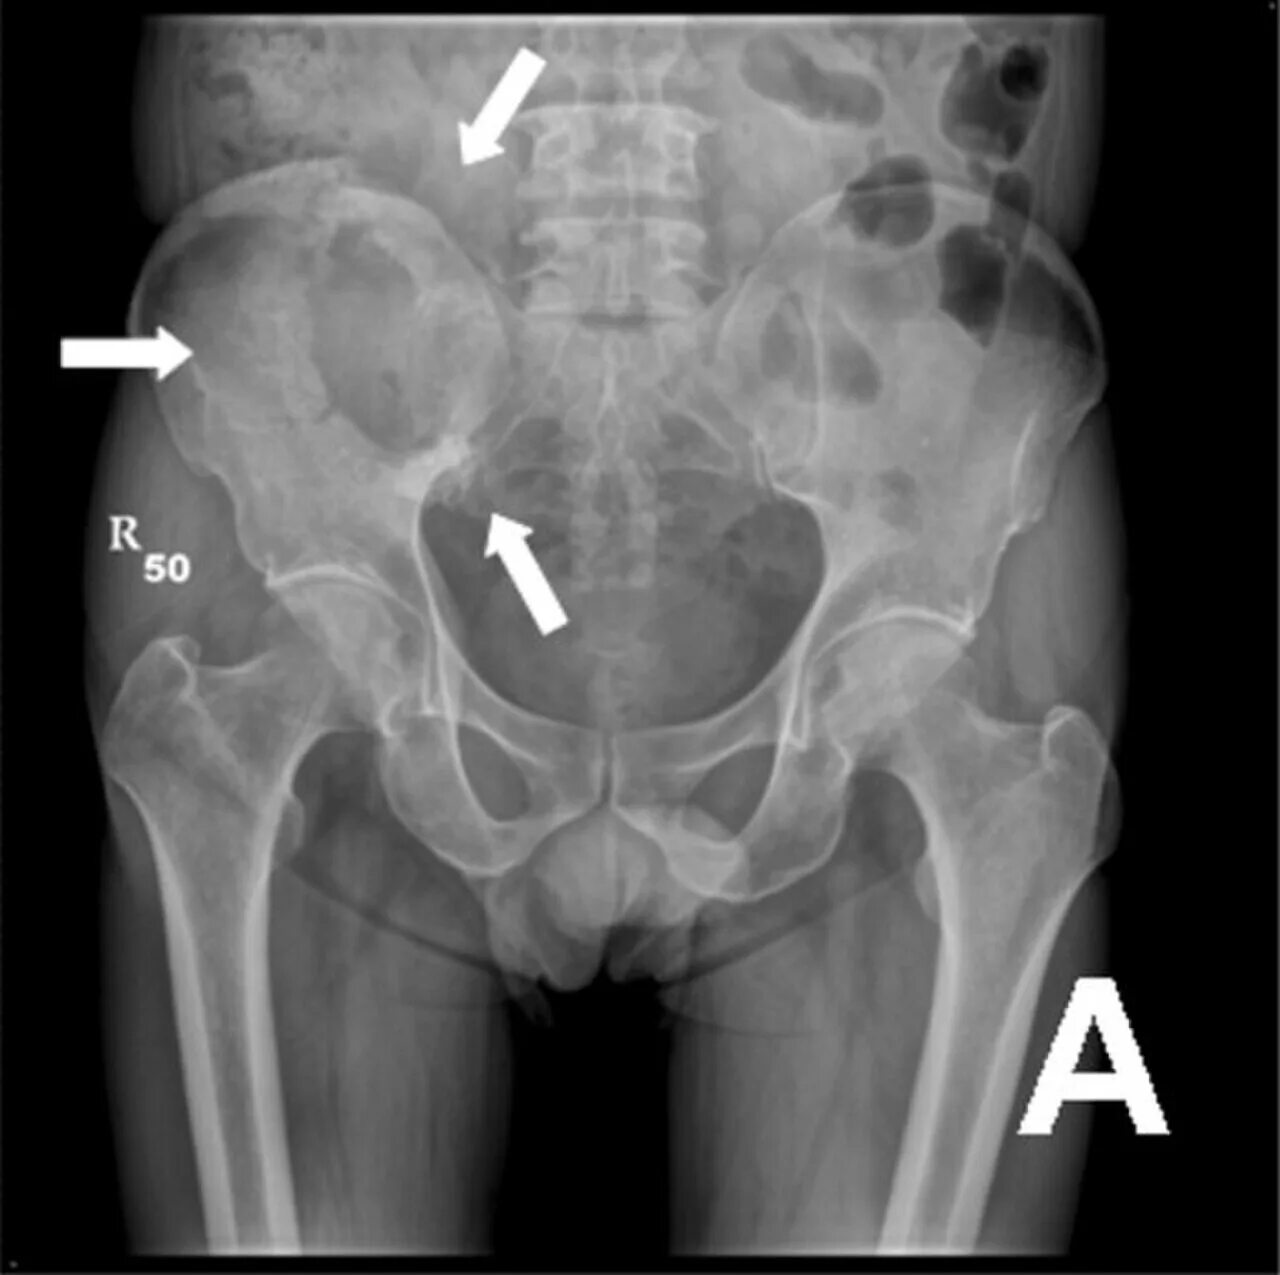

Метастазы в тазу